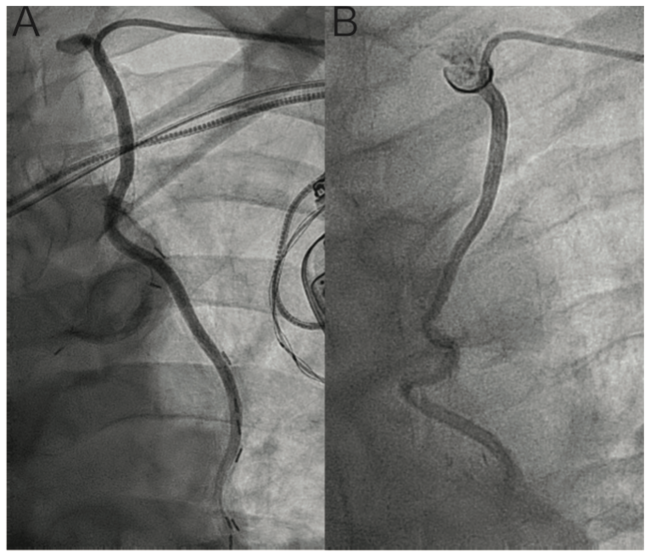

Description of MOT-C catheter. The MOT-C catheter was designed by interventional radiologist Amir Motarjeme for thrombolytic therapy of the iliac arteries.4 The catheter is manufactured by Merit Medical and is available as a 4- or 5-Fr, 100-cm diagnostic catheter with an 0.040˝ inner lumen diameter and is available for routine clinical use. The catheter tip shape resembles a Rösch inferior mesenteric (RIM) catheter, but is available in a length that facilitates radial access angiography of the IMA (Figure 1A). The soft curve of the tip of the catheter approximates the angle of take-off of the IMA from the subclavian artery better than the traditionally used IMA catheter (Figure 2 and Supplemental Video).

Catheterization technique. The catheter is advanced over an 0.035˝ guidewire from radial or ulnar access into the ipsilateral subclavian artery just proximal to the IMA origin. The wire is removed and the catheter is gently withdrawn with its tip directed inferiorly toward the IMA, where it atraumatically engages the ostium of the vessel with excellent selectivity (Figure 2A). If the catheter is out of plane with the ostium of the IMA, gentle clockwise or counterclockwise rotation can be used to engage vessels with anterior or posterior take-offs. After selective angiography is performed, the catheter can be withdrawn into the subclavian and removed over a guidewire.